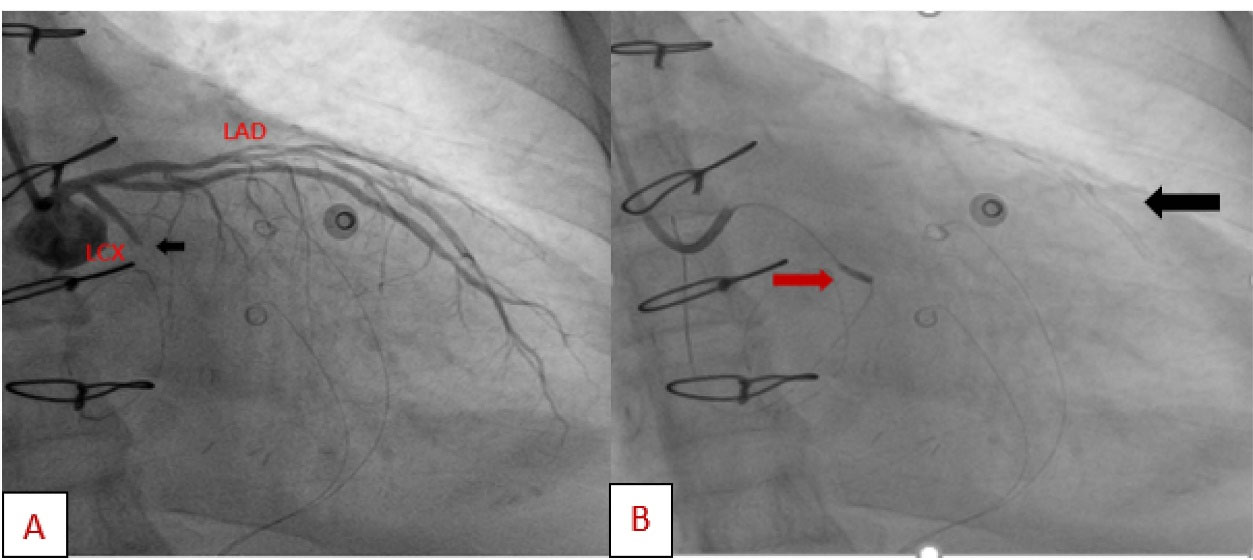

A 57-year-old lady with history of rheumatic mitral valve disease underwent mitral valve replacement by Saint Jude Medical Epic bioprosthesis in our high-volume mitral surgery center. Preoperative coronary angiography was non-significant except for a moderate stenosis of mid left anterior descending artery (LAD) (). The patient underwent coronary artery bypass grafting (CABG) using left internal mammary artery (LIMA) to LAD concomitantly with mitral valve surgery. The surgery was smooth with no postoperative complications. On serial postoperative electrocardiogram (EKG), there was no ST segment elevation or new significant ischemic changes compared to preoperative EKG. Routine postoperative echocardiogram showed good function of the mitral prosthesis and good global function of the left ventricle. Four weeks later, the patient started to have dyspnea, orthopnea and other symptoms of heart failure. EKG showed non-significant ST-T changes (). Echocardiography showed severely impaired left ventricle (LV) systolic function. Moreover, there was a localized hematoma adjacent to the right atrium without hemodynamic impact (). In light of these findings along with elevated troponin level, we decided to repeat coronary angiography. The later showed complete occlusion of the proximal LCX () and stenosis of the LIMA -LAD anastomosis. A PCI strategy was successful for LIMA-LAD stenosis () but difficult for LCX lesion; after crossing the lesion using work-horse wire, and use of different size non-compliant and compliant balloons, there was continuous recoil after balloon deflation (). The trial of angioplasty and stenting was failed with no recuperation of distal flow. Therefore, we suspected surgical complication with mechanical compression of the circumflex coronary artery most probably by encircling suture loop, in addition to stenosis of the LIMA-LAD. Furthermore, the retro atrial hematoma might be caused by epicardial coronary artery injury. The procedure was then stopped and the patient was kept on medical treatment. On follow up visits, there was complete resolution of the atrial hematoma, and a significant improvement of LV function on standard heart failure treatment.

jcvtr-14-268-g004

Figure 4. (A) Coronary angiography shows proximal LCX stenosis (black arrow). (B) Trial of PCI of the circumflex coronary artery, the balloon (red arrow) had crossed easily but failed to dilate the lesion. Successful angioplasty of LIMA-LAD stenosis, stent is shown (black arrow), PCI; percutaneous coronary intervention.